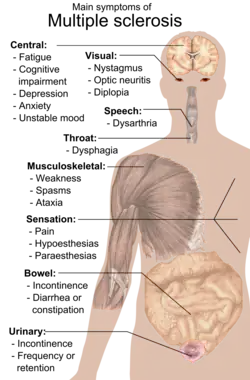

En person med MS kan lide under næsten alle neurologiske symptomer eller tegn, inklusiv ændringer i fornemmelser (hypæstesi og paræstesi), muskelsvaghed, muskelkramper eller besvær ved bevægelser; vanskeligheder med koordination og balance (ataksi), problemer med talen (dysartri) eller synkebesvær (dysfagi), synsforstyrrelser (nystagmus, optisk neuritis[9] eller dobbeltsyn), træthed, akut eller kronisk smerte samt blære- og tarmproblemer.[1] Kognitiv svækkelse i varierende grad og emotionelle symptomer på depression eller ustabilt humør er også almindeligt.[1] Uhthoffs fænomen, en forværring af eksisterende symptomer grundet udsættelse for temperaturer, der er højere end normalt, og lhermittes tegn, en elektrisk følelse, der løber langs ryggen, når man bøjer nakken, er særligt karakteristiske for MS, men er ikke udelukkende tilknyttet sygdommen.[1] Det primære kliniske mål for handicappenes progression og symptomernes alvor er Expanded Disability Status Scale (EDSS).[10]